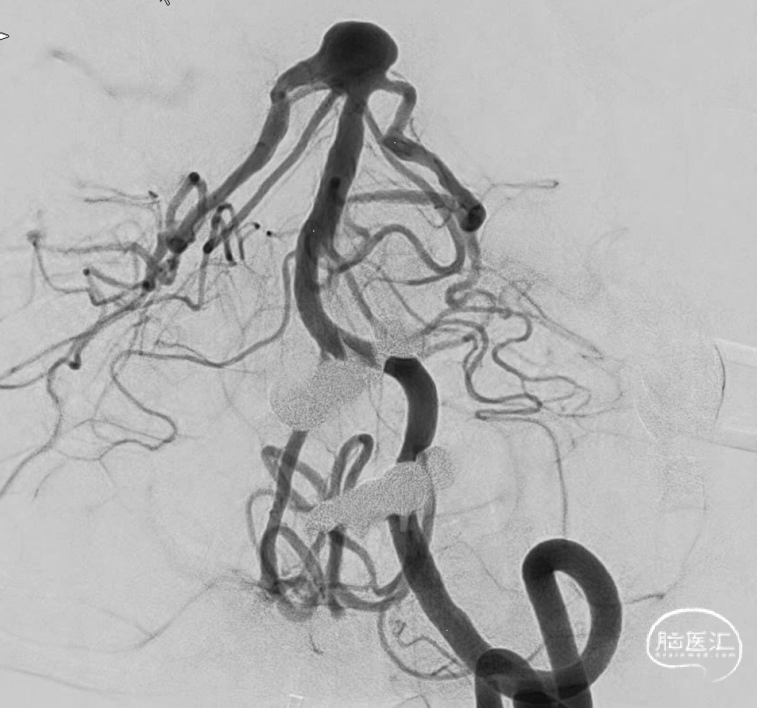

“又是它,大大的瘤,宽宽的颈,实则像个水母”。

虽然棘手,但是也得设计,一个未破裂的动脉瘤。家里比较积极,那就做吧。但是得清楚越安全越好,毕竟没有症状。不管用一个还是两个支架,一切按Y型支架准备。于是乎,双鞘给上。考虑到以往经验,按照自己怎么方便怎么来,右侧鞘安排6F导引导管,操作方便,可以放支架,填弹簧圈。左侧鞘就放个5F导引导管吧,放个支架就完事。